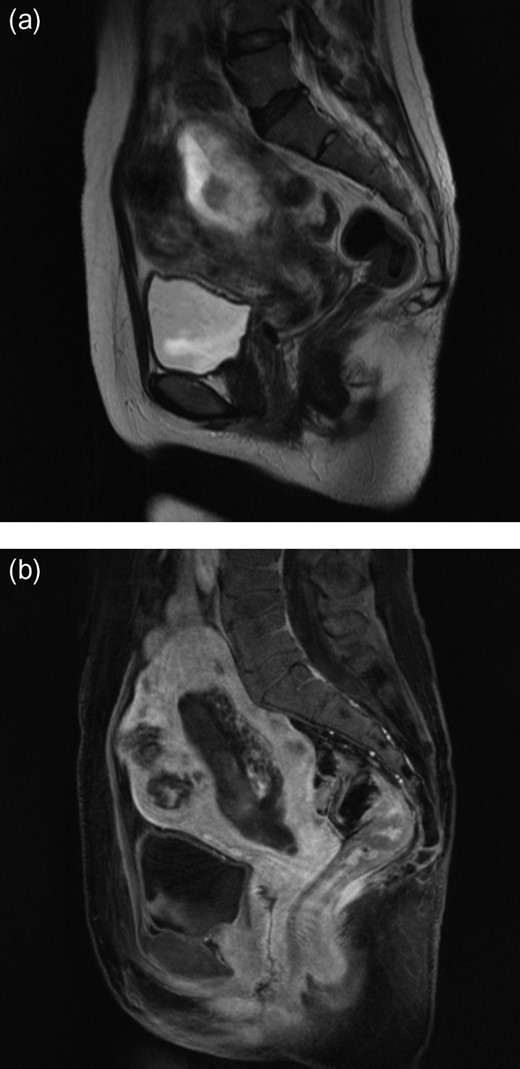

A 50-year-old woman, Gravida 3, Para 1, presented to our department with irregular genital bleeding for 2 months. Her last menstrual period had been 2 months before. Her obstetrical history included a normal vaginal delivery 13 years before and two spontaneous abortions 8 and 11 years previously. Transvaginal ultrasonography showed an enlarged uterus with endometrial thickening with an echogenic pattern (Fig. 1). As endometrial cancer was suspected first, an endometrial biopsy and magnetic resonance imaging (MRI) were performed. The endometrial biopsy revealed decidual tissues, and the MRI revealed invasion of a uterine corpus tumor into the myometrium (Fig. 2). A week later, the patient admitted to the hospital with continuation of irregular vaginal bleeding. Second endometrial biopsy was done and serum β-human chorionic gonadotropin (hCG) level was also measured owing to suspicion of a hydatidiform mole. The serum hCG level was over 225 000 mIU/mL, and the endometrial biopsy revealed a complete hydatidiform mole. Because the patient's hemoglobin level was 7.0 g/dL, owing to the continuation of uterine bleeding, we transfused 800 mL of red cell concentrate and discharged the patient. A lung metastasis, 1 cm in diameter, was observed on a contrast computer tomography scan (Fig. 3), and an invasive mole with lung metastasis was diagnosed. Because the patient did not desire preservation of her uterus or adnexa, we offered her a total abdominal hysterectomy (TAH) and bilateral salpingo-oophorectomy (BSO). At her next consultation for the continuous genital bleeding, a tumor of the right labium minus was recognized and histologically confirmed as a metastatic lesion of the mole (Fig. 4). The patient underwent TAH and BSO. Unfortunately, a tumor of right labium minus had spontaneously fallen off during surgery. In a gross specimen, molar vesicles were recognized at the uterine corpus with the right ovary a little swollen (Fig. 5). The invasions into myometrium by both villi and the trophoblasts were histopathologically confirmed (Fig. 6). In addition to the labium minus tumor, a metastatic lesion of the right ovary was diagnosed. The final pathological diagnosis was metastatic invasive hydatidiform mole, Stage III. The patient's serum hCG level fell to 10 779 mIU/mL after her operation. The patient was then started on administered methotrexate 20 mg/body intramuscularly, 5 days a week at 2 weeks intervals. Serum hCG levels are measured for the estimation of chemotherapy [4]. Her serum hCG level rapidly fell to 1.2 mIU/mL after four courses of methotrexate (Fig. 7). Two additional courses of methotrexate were completed, and there has been no evidence of recurrent disease for 6 months.

Contrast computed tomography scan showing the metastasis in the lungs.